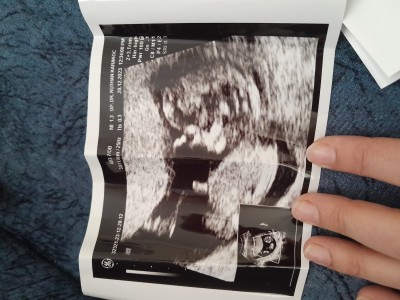

Kızlar 11+6 da doktor kiza benziyor ama kesin değil dedi yan durunca erkekde olabilir dedi özelde. Anlayan varsa bakabilirmi çok merak ediyorum

Gebelik haftası 15